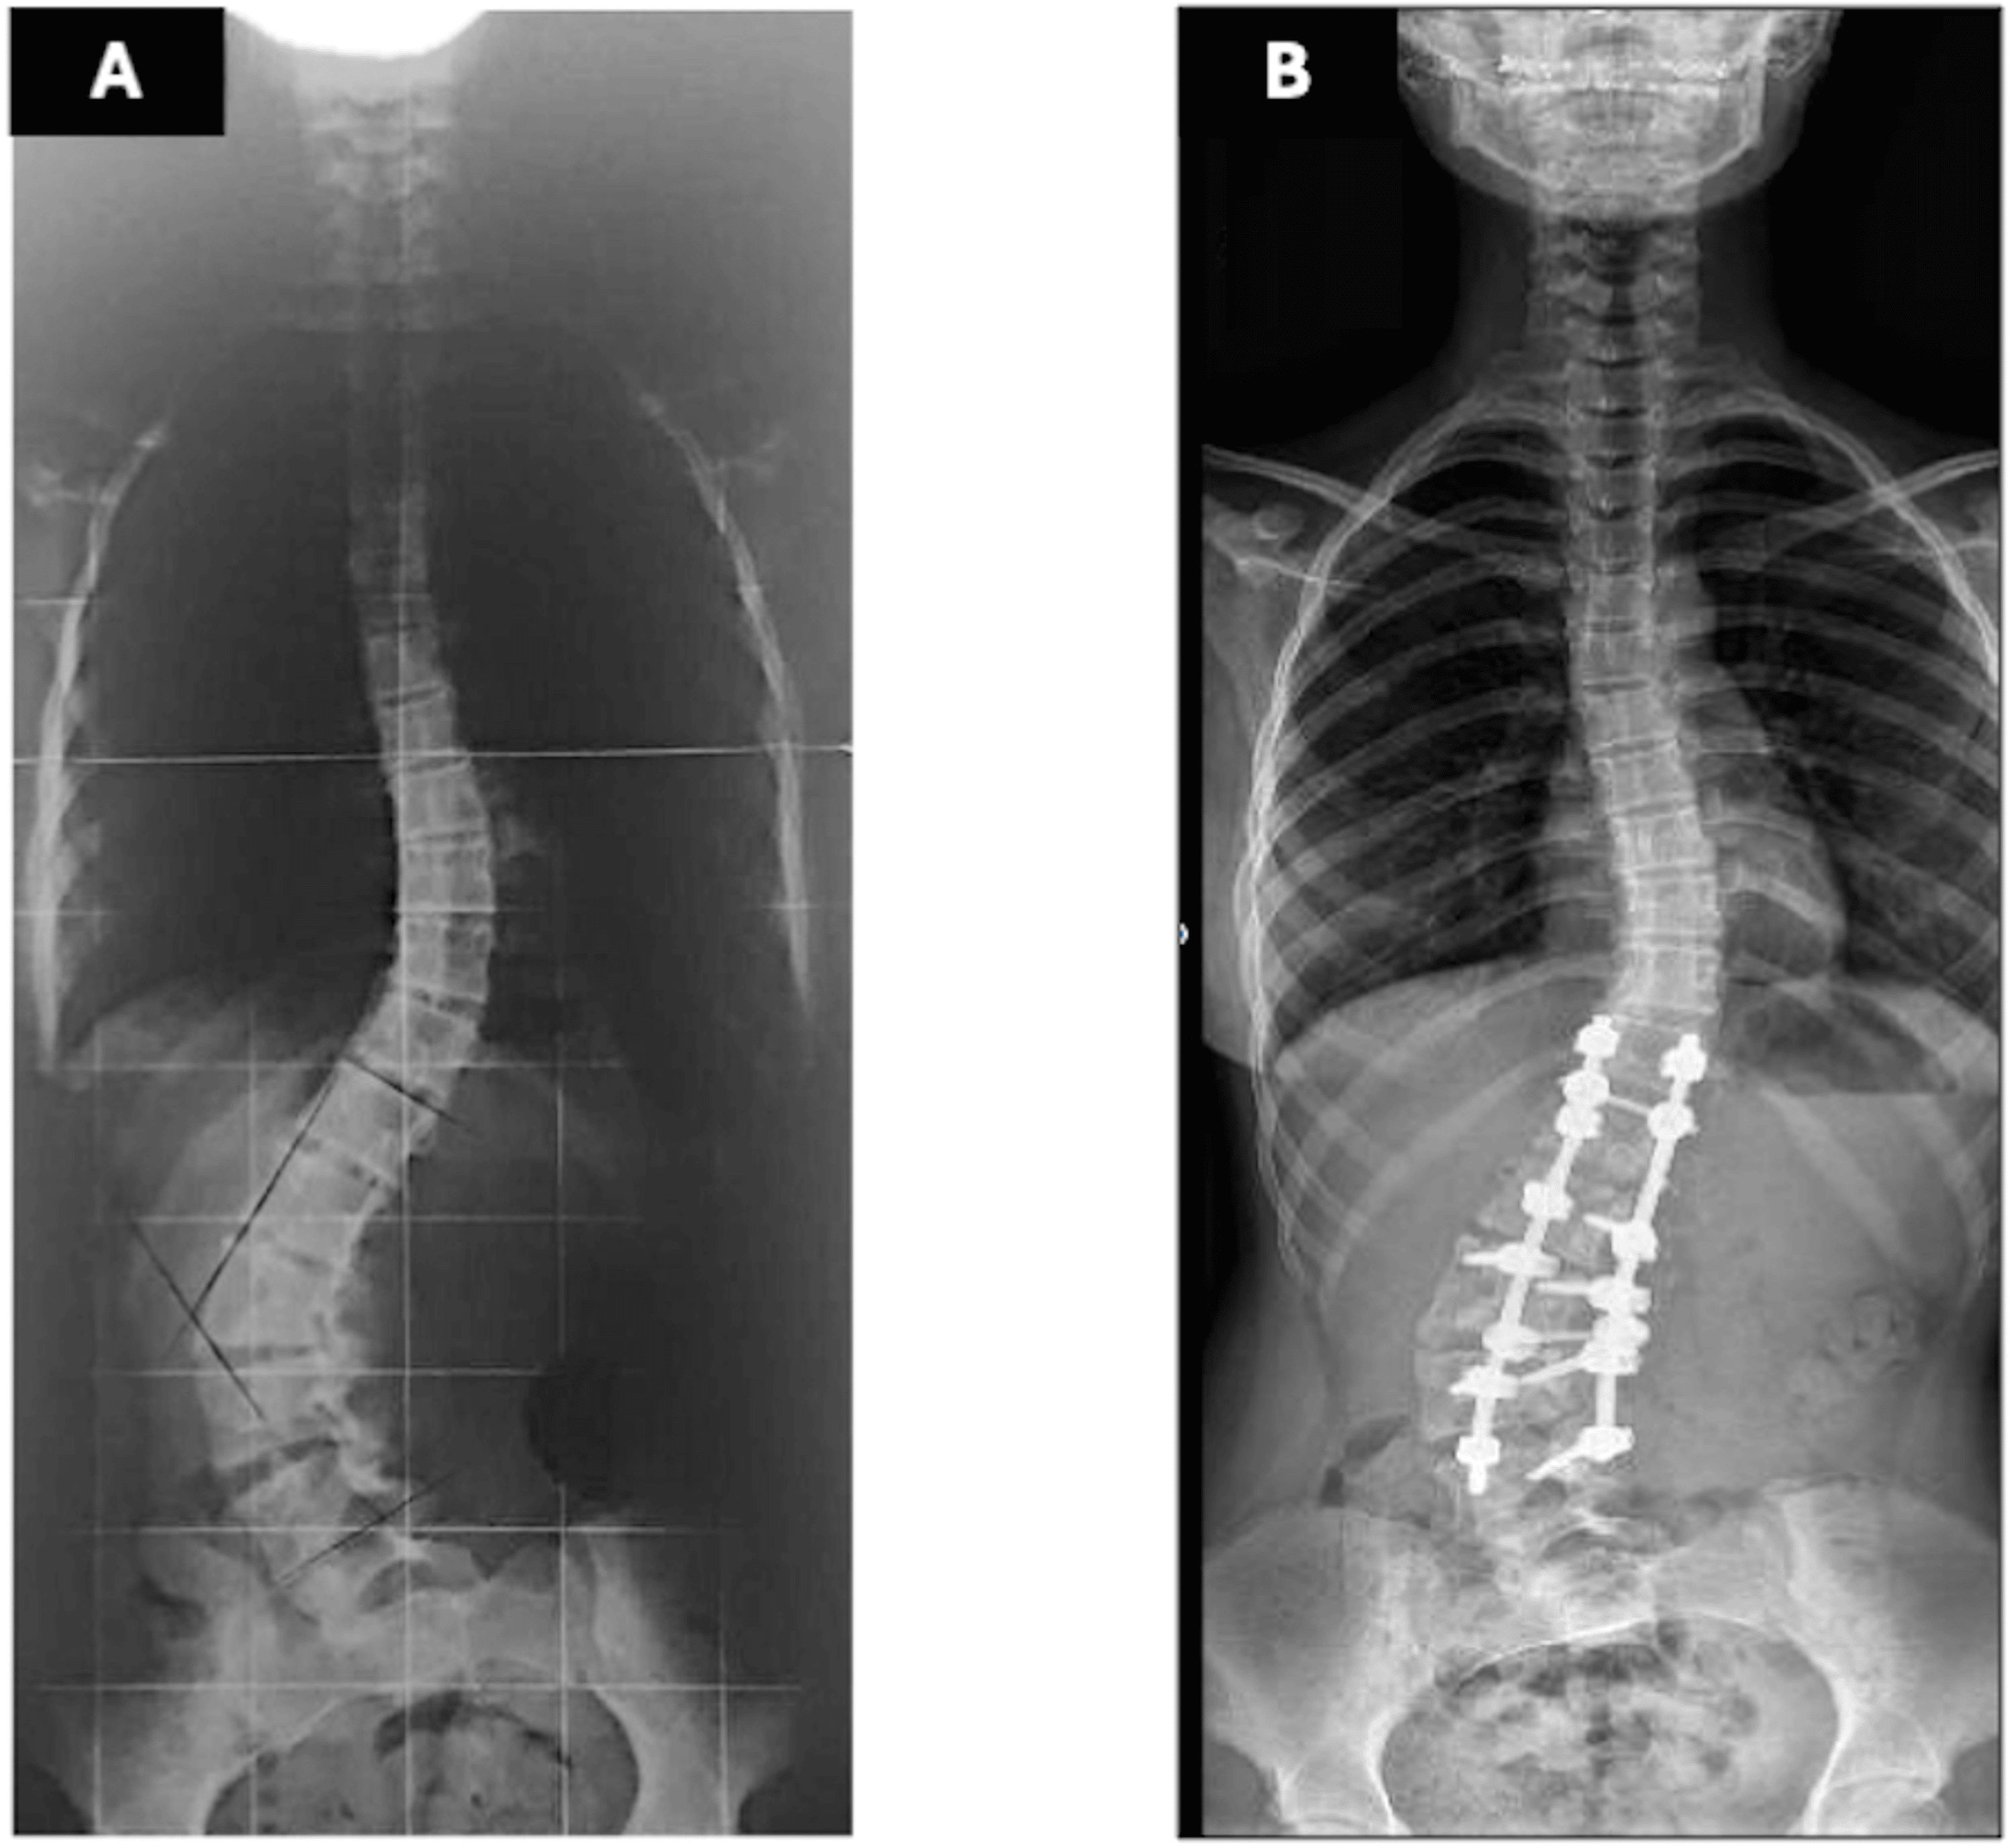

Radiographs demonstrated a 67° lumbar scoliosis due to an L3 hemivertebra fused ventrally and dorsally with L4. Previous imaging showed progression from 22° at age eight to 54° at age 11. Preoperative laboratory tests were within normal limits, including hemoglobin of 13.6 g/dL (reference range: 12.0-14.0 g/dL) and hematocrit of 40% (reference range: 36-43%). Preoperative traction radiographs demonstrated partial curve correction to 37° (Figure 1a). A computed tomography (CT) evaluation confirmed the previously described characteristics, including a 67° lumbar scoliosis caused by a ventral and dorsal fusion of L3 and L4 vertebrae. Additionally, the preoperative CT scan revealed that the IVC and aorta were located within the concavity of the spinal curve, a finding commonly observed in scoliosis cases. No other abnormalities were detected in other organs.

The patient was positioned prone on an Allen table. Bilateral pedicle screws were placed from T12 to L5, preserving the hemivertebra and L6. (L6 in orthopedic terminology denotes the lumbarization of the first sacral vertebra. This condition implies that the vertebra functions in a manner akin to a lumbar vertebra, rather than being an additional lumbar vertebra in the strict anatomical sense.) A 5.5-mm rod was inserted on the convex side, and vertebral derotation was attempted to convert the scoliotic curve into a lordotic alignment. During this maneuver, the patient developed profound hypotension (Mean Arterial Pressure < 50 mmHg) and tachycardia (heart rate > 140 bpm). Despite volume resuscitation and vasopressor administration (ephedrine and phenylephrine), hemodynamic stability was not maintained; however, approximately three minutes after reversing the derotation, blood pressure and heart rate recovered immediately. A subsequent vertebral derotation attempt made ten minutes later resulted in the recurrence of the same hemodynamic disturbance, which again resolved upon reversing the maneuver. Consequently, the surgical team opted to perform the vertebral derotation gradually, continuously monitoring hemodynamic parameters and reversing the maneuver incrementally at the first sign of instability until complete recovery was achieved. Because the correction achieved by derotation was deemed insufficient, an in-situ rod-bending technique was subsequently applied to obtain partial deformity correction (Figure 1b). Somatosensory and motor evoked potentials remained unaltered throughout the procedure. The surgery was completed without further complications, with an estimated blood loss of 500 mL and the administration of 2000 mL of Lactated Ringer’s solution.

Initially, an anterior-posterior hemivertebra resection was proposed to the family. However, after discussing the associated risks, the family declined this option. An alternative approach aimed at achieving sub-optimal correction using pedicle screws and the convex rod rotation technique was then advised. This method was discussed and agreed upon by both the parents and the patient. Nevertheless, severe hemodynamic instability occurred during both attempts at this maneuver, it was deemed necessary to modify the primary correction technique to an in situ rod-contouring technique. This technique is one of the corrective maneuvers described for severe and rigid scoliosis and is typically employed in conjunction with other techniques [7].